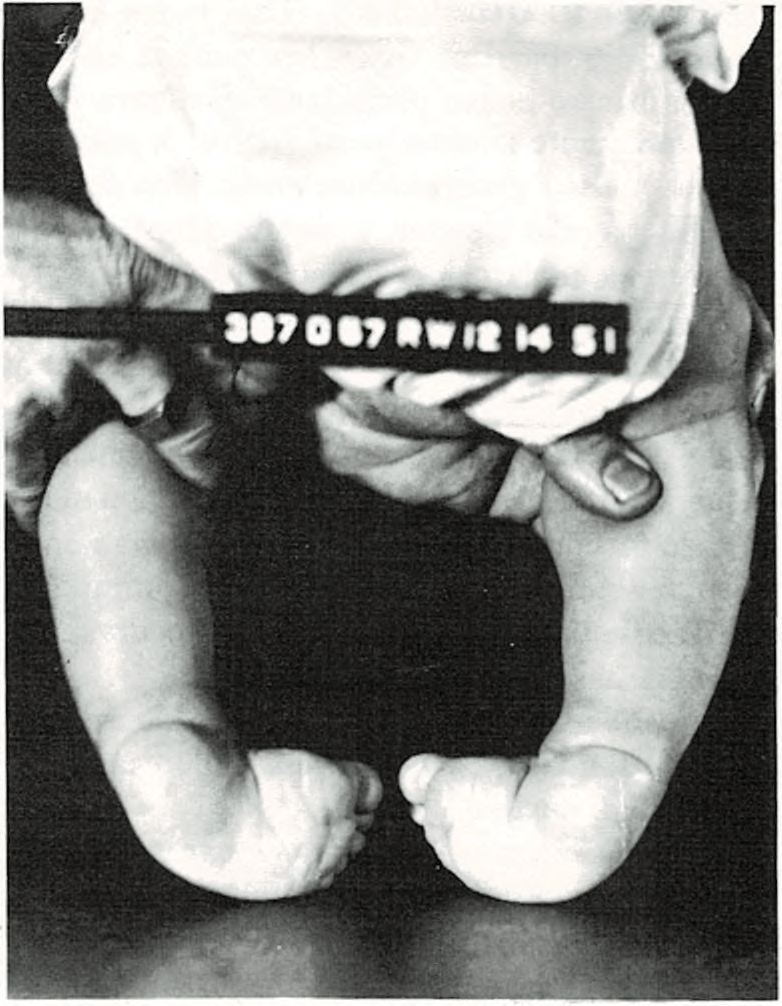

La deformación denominada del “pie zambo” es la más común con la que

Se comenzó tratamiento correctivo antes del año de edad.

puede nacer un niño. Generalmente el pie zambo, llamado también pie varo, está torcido hacia dentro y hacia abajo, lo que produce una deformación típica en las extremidades inferiores. Se presenta en determinadas familias y es más común en los niños que en las niñas. Ocurre una vez entre 1.000 nacimientos.

Se puede presentar en uno o en ambos pies y la gravedad oscila entre las formas leves hasta las más importantes que necesitan un cuidado muy especial. Este último caso será el cirujano ortopedista (especialista en alteraciones de los huesos) el que lo dirija. El tratamiento incluye masajes, zapatos especiales, tablillas correctoras o yesos y, en algunos casos, una operación. Los mejores resultados se obtienen cuando se comienza el tratamiento preferentemente antes de que el niño tenga un año de edad. Si se retrasa, puede ser más difícil la corrección de la deformidad y los resultados no tan buenos.